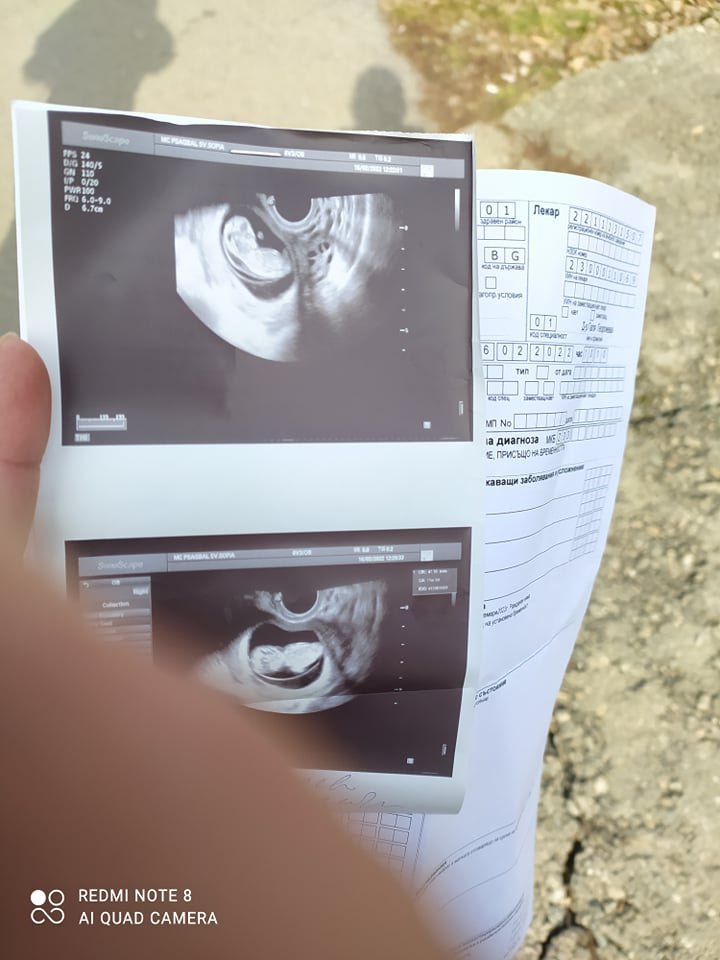

Снимката е на 11 седмици и 6ти ден

От снимката може ли да се разгледа увреждане на плода?

Изглежда сякаш НТ е голяма и има съмнения за аномалии.

Направете хорионбиопсия или амниоцентеза, за да се отхвърли или потвърди диагноза.

Не бързайте с аборта, преди да са направени допълнителни изследвания.

В момента сме 11та седмица и имахме преглед тази седмица и казаха, че спешно трябва да се отстрани с контракции, защото има проблем.

Аз обаче настоях да пусна снимката на още 2-3 места, защото нямам доверие на медицината в България, което е очевиден фактор масово. Има разминаване в информацията и предположих, че тук във форума ще има още някой да погледне само и да изкаже мнение до колкото е възможно.